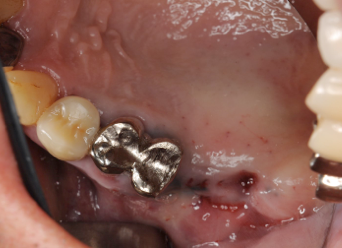

4ヶ月後の患部、もう一度サイナスリフトをアプローチ

4ヶ月経つとこのように前回骨を削ったところもこのようにきれいに再生しています。粘膜も一度触っているので再生してことによって厚みがでて、剥離もしやすくなっています。